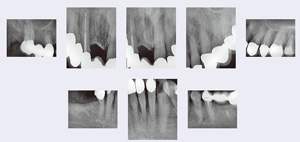

影像檢查

在第一次就診時(shí)患者并沒(méi)有帶來(lái)她的X 線片。在2013年10 月15 日為其拍攝了8 張X 線片(圖7)。結(jié)果顯示,上頜和下頜的前磨牙和磨牙區(qū)域(不包括37 號(hào)牙齒)牙槽骨水平喪失≤25%的牙根長(zhǎng)度。上頜前牙及42 號(hào)牙齒的水平骨喪失≤50%的牙根長(zhǎng)度,而32、31 和41 號(hào)牙齒的骨喪失則達(dá)到>50%的根長(zhǎng)度。16、14、27 和35 號(hào)牙齒顯示根充不完全,35 號(hào)牙齒在X 線片上顯示X 線阻射的根充材料只達(dá)到根長(zhǎng)度的一半,而16 和14 號(hào)牙齒X 線片甚至顯示沒(méi)有X 線阻射的根管充填材料,根尖周骨質(zhì)溶解。在36 區(qū)域可以看到一個(gè)無(wú)刺激癥狀的殘根。33 號(hào)牙齒近中齲壞,43號(hào)牙齒近中繼發(fā)齲。下頜前牙區(qū)域可見(jiàn)明顯的牙結(jié)石。

圖7:2013 年10 月15 日的影像學(xué)檢查。